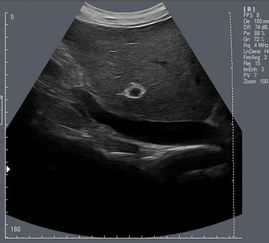

B超V6系统是一款集成了多项先进技术的医疗影像设备,它采用了先进的超声波成像原理,通过发射和接收超声波,对人体的内部器官进行无创、实时、动态的成像。B超V6系统具有体积小、操作简便、成像清晰等特点,广泛应用于临床医学的各个领域。

2. 肝胆胰脾科:B超V6系统可对肝、胆、胰、脾等器官进行成像,有助于诊断相关疾病。

5. 普通外科:B超V6系统可对腹部、甲状腺、乳腺等器官进行成像,有助于诊断相关疾病。